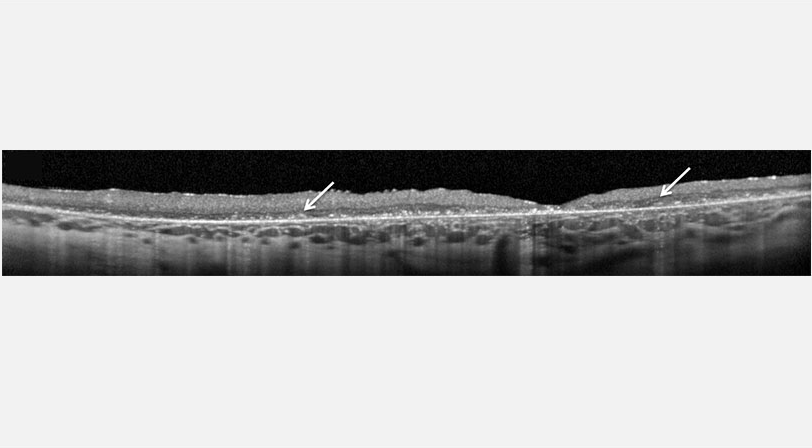

Nota: esta imagen pertenece a un paciente de 8 años y refleja los avances en la fase avanzada de la CLN2.6

Tomografía de coherencia óptica (TCO)

La TCO puede mostrar la progresión de la CLN2 por medio de la degeneración de la retina y la acumulación de material hiperreflexivo.6,7